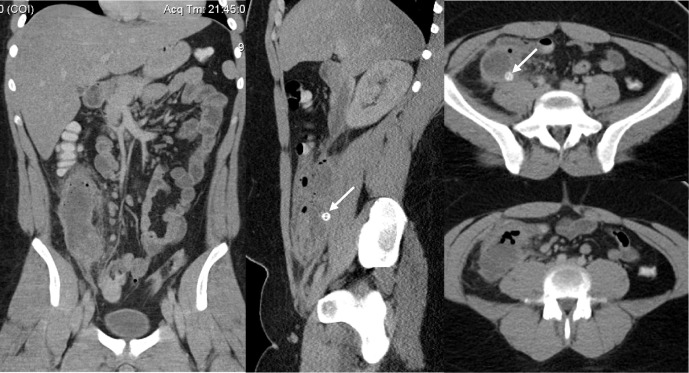

Abdominal CT Scan

Interpretation

Compared results with ultrasound findings. Appendicitis confirmed with slightly ruptured appendix.